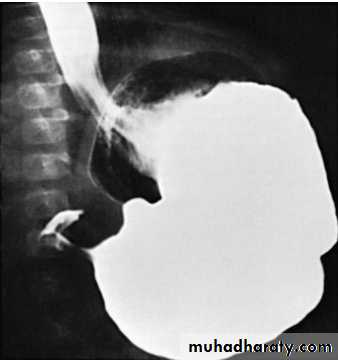

• Contrast studies demonstrate an elongated pyloric channel (string sign), a bulge of the pyloric muscle into the antrum (shoulder sign), and parallel streaks of barium seen in the narrowed channel, producing a “double tract sign”

Barium in the stomach of an infant with projectil

The attenuated pyloric canal is typical of CHPS.• DDx: